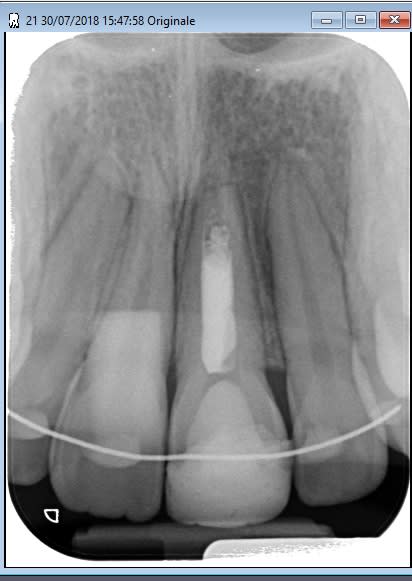

J'ai retrouvé ça, endo réalisée en 2012 (7 ans) sur trauma+nécrose.

Radio en 2018, on note le pont dentinaire.

Je pense qu'il s'agit d'un cône ajusté+pâte, une interséance au CaOH a été réalisée.

(edit: et j'ai vérifié sur les radios précédentes, le profil d'émergence en distal, c'est la colle odf, ce n'était pas présent avant traitement.)